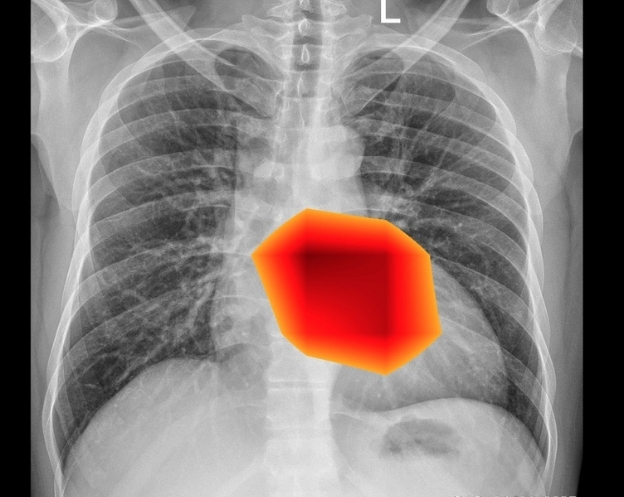

CARDIOMEGALY

View Detection

• Explainable AI: Visual heatmaps and clear rationale for every detection